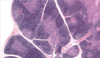

CARACTERISTICAS HISTOLOGICAS DEL GANGLIO LINFATICO

La cápsula, compuesta por tejido conjuntivo denso que rodea al ganglio.

Los cordones o trabeculas, compuestos por tejido conjuntivo, el cual se extiende desde la cápsula hacia el parénquima del ganglio para formar un armazón grueso.

La corteza, constituido principalmente POR TEJIDO LINFOIDEO NODULAR.

La paracorteza, constituido por tejido linfático difuso.

La medula, donde se aloja los vasos linfáticos.